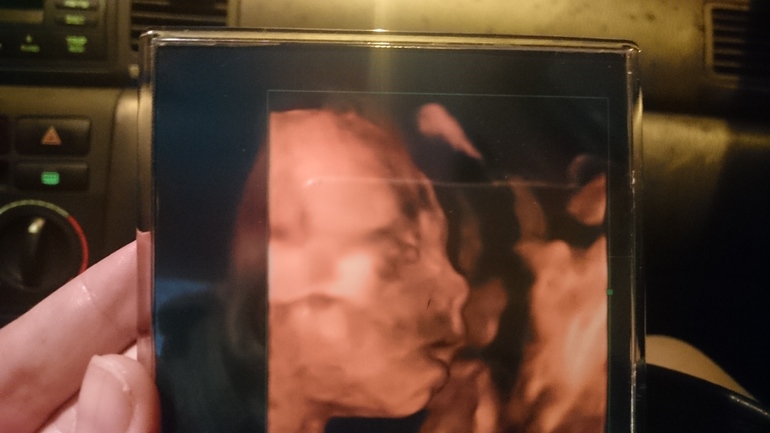

УЗИ, КТГ, доплерСделала я узи, точнее скрининг. Вообще, хочу сказать,что после этого длительного давления на мой живот датчиком, весь низ живота долго ныл после. Одно дело быстро посмотреть,а другое дело около 30 минут просвечивать меня и малышку. Да! Подтвердилось,что мы ждём доченьку 🤗 Это так здорово! Все у нас хорошо, кроме обхвата талии,она у нас 162 при норме до 160 мм))) Муж вообще вышел из кабинета со словами :все хорошо, но вот попа большая)))))) я говорю,не попа)) а талия)) в целом,меня это не сильно беспокоит. Вот добавлю ещё для вас фотографию моей сладусечки 😘